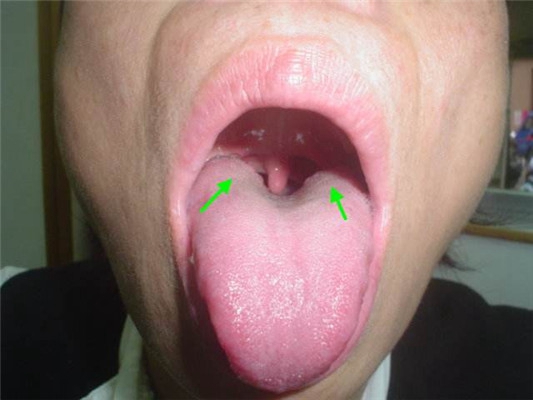

慢性咽喉炎圖片

喉部淋巴濾泡增生 (44)